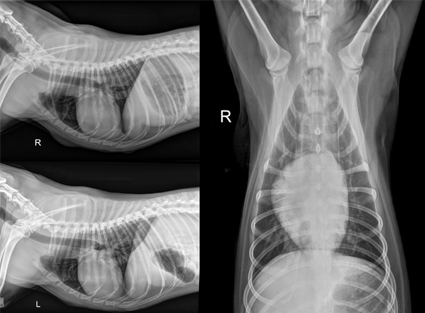

Radiología Digestiva

- Estudios con contraste (esófago, estómago, intestinos)

- Detección de cuerpos extraños

- Evaluación de obstrucciones intestinales

Estudios con Contraste

- Tránsito gastrointestinal

- Urografía (vías urinarias)

- Cistografía (vejiga)

- Fistulografías